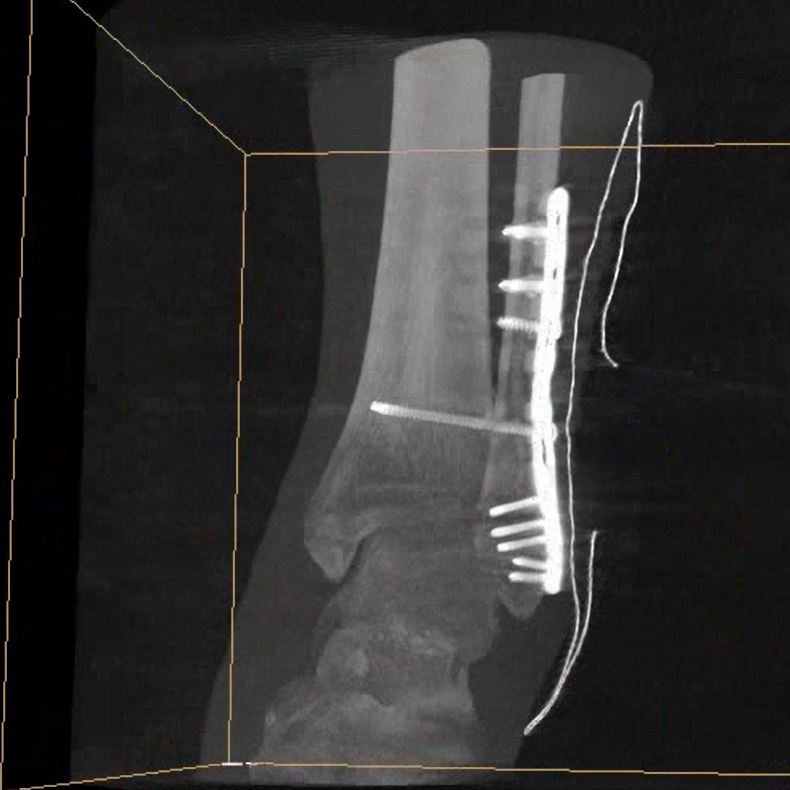

術(shù)中三維成像和橫斷面圖像提供多角度的手術(shù)診斷信息,輔助醫(yī)生進(jìn)行術(shù)中評(píng)估判斷,諸如骨折復(fù)位情況和內(nèi)植入螺釘?shù)某叽绾臀恢茫o助手術(shù)更好地完成。